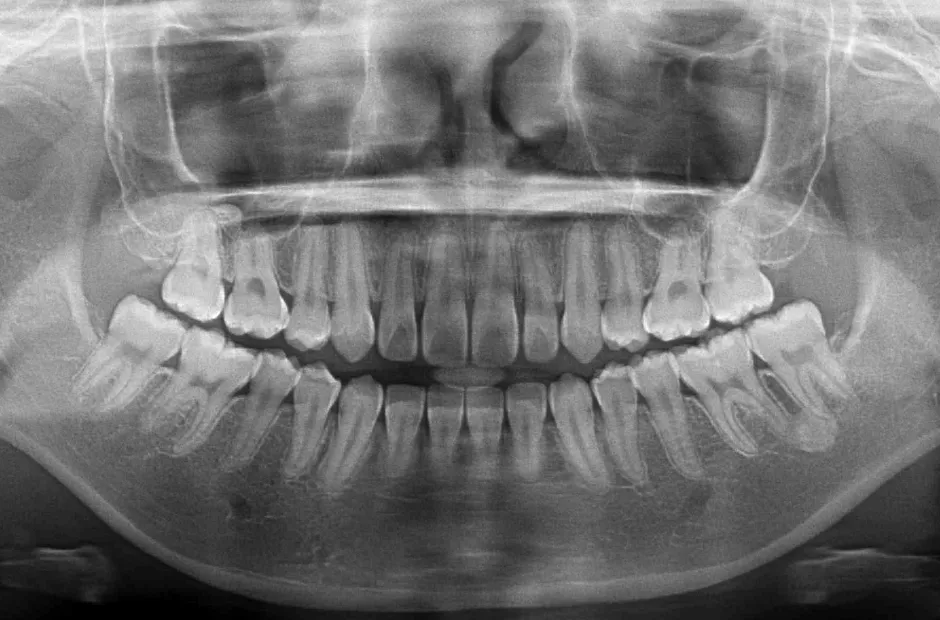

叢生

| 診断名・主訴 | 叢生 |

|---|---|

| 年齢・性別 | 43歳・女性 |

| 治療期間・回数 | 2年7か月 27回 |

| 治療に用いた主な装置 | 舌側矯正 |

| 抜歯部位 | 両顎4,4 |

| 治療費 | 100万円(税抜) |

| リスク・副作用 | 装置による違和感・疼痛・歯肉退縮・歯根吸収・虫歯のリスクなど |